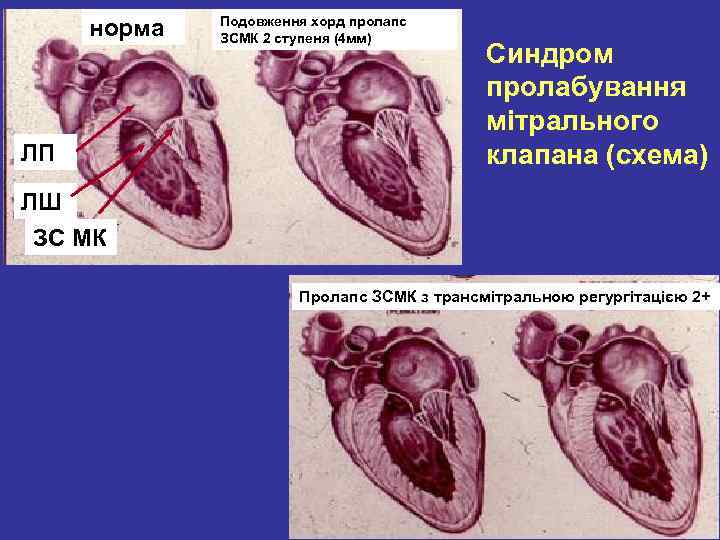

СИНДРОМ ПРОЛАБУВАННЯ КЛАПАНІВ СЕРЦЯ характеризується прогинанням стулки (стулок) в просвіт передсердь, розширенням кілець мітрального та трикуспідального клапанів Стани, при яких зустрічається ПМК Захворювання сполучної тканини: синдроми Марфана, Ейлера- Данлоса, Рейно, ревматоїдний артрит Вроджені вади серця: ASD, VSD, аномалія Ебштейна, тетрада Фалло, аневризма міжпередсердної перетинки Синдроми ССВ, WPW, КЛК, Романо-Уорда (QT) Кардіоміопатії: ДКМП, ГКМП, РКМП b Ішемічна хвороба серця (ГІМ, ГКС, ССН) та інші Середня частота в популяції складає 2, 5 -5%, найбільш часто зустрічається у віці 20 -29 років, частіше у людей астенічної статури

СИНДРОМ ПРОЛАБУВАННЯ КЛАПАНІВ СЕРЦЯ Класифікація Н. М. Мухарлямова (1981) За формою: 1. Вроджений ПМК (ізольований чи в поєднанні з синдромами Марфана, Ейлера-Данлоса) 2. Набутий (вторинний) ПМК (ревматизм, ІХС, ДКМП, ГКМП, травма) 3. Ідіопатичний ПМК За числом уражених стулок: однієї (передньої, задньої), обох За ступенем вираженості пролабування стулок: І ступінь до 3 мм, ІІ ступінь до 6 мм, ІІІ ступінь до 9 мм і більше За наявністю порушення гемодинаміки: без регургітації, з регургітацією І, ІІІ ступеня За перебігом: безсимптомний, легкий, середньої важкості, важкий

СИНДРОМ ПРОЛАБУВАННЯ КЛАПАНІВ СЕРЦЯ Скарги: • дискомфорт в ділянці серця, запаморочення, серцебиття, епізоди епритомності, колючий або тиснучий біль в грудній клітці, задишка, загальна слабість, відчуття страху смерті, порушення ритму При аускультації - систолічне клацання посередині систоли Двомірна Ехо. КГ: систолічне зміщення передньої (задньої) стулки в ліве передсердя, потовщення стулок МК, розширення мітрального кільця. Доплер- Ехо. КГ: регургітація через пролабуючий клапан в ліве передсердя та збільшення його діаметра

норма ЛП Подовження хорд пролапс ЗСМК 2 ступеня (4 мм) Синдром пролабування мітрального клапана (схема) ЛШ ЗС МК Пролапс ЗСМК з трансмітральною регургітацією 2+